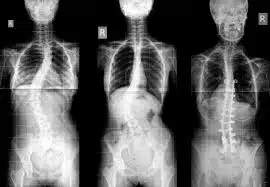

الجنف (انحراف العمود الفقري) يعني أن العمود الفقري غير مستقيم ويكون منحنياً إلى أحد الجانبين. تتراوح درجات ميلان انحراف العمود افقري (الجنف) بين الانحراف الخفيف أو المتوسط أو الشديد ، ويعتبر جنفاً إذا كانت زاوية الانحناء أكثر من 10 درجات. وكلما زادت زاوية منحنى العمود الفقري ، زادت احتمالية تفاقمه بمرور الوقت. قد لا تتمكن من تشخيص هذه المشكلة بسهولة من خلال النظر مباشرة إلى العمود الفقري لشخص ما ، ولكن قد تلاحظها عندما يقف لأنه يتسبب في ميلان المريض قليلاً أو يكون لديه عدم تساو في ارتفاع أكتافه أو وركه.

عندما تصل درجة الجنف لمراحل متقدمة 40 أو 50 درجة ، ينصح الأطباء المريض بإجراء الجراحة، سواء كان المريض مراهقاً أم بالغاً. يوصى بالإجراء الجراحي عندما تكون درجة المنحنى 50 وعندما يعاني المريض من تلف الأعصاب في الساقين أو الوعاء أو يسبب مشاكل في المثانة. عادة ما تتطور حالات الجنَف الحادة بمرور الوقت، لذا فإن طبيبك قد يقترح إجراء جراحة الجنَف لخفض حدة انحناء العمود الفقري ولمنع تفاقم الحالة. إن أحد أكثر أنواع جراحة الجنف شيوعاً تسمى دَمْج الفقرات.